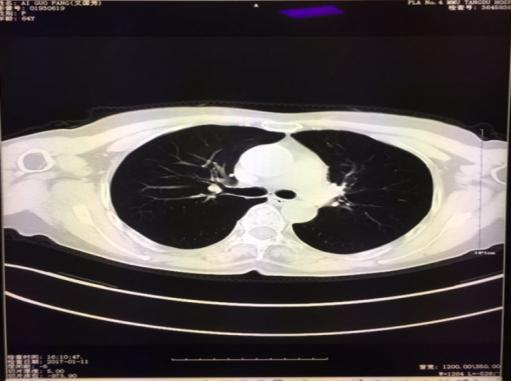

病例2 李某 因面部浮肿,胸部CT显示纵隔淋巴结多处肿大,经过EBUS-TBNA(经支气管粘膜超声纵隔淋巴结穿刺术),取出标本,病理证实为”纵隔淋巴结肉芽肿”,符合结核,抗结核治疗1月后明显好转。